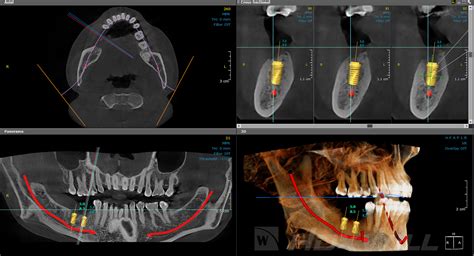

La exploración mediante tac dental o tomografía computarizada para el diagnóstico maxilofacial debe ser efectuada con equipos que dispongan de programas informáticos de reformación multiplanar (MPR). La tomografía computarizada de haz cónico (TCHC), más comunmente conocida por sus siglas inglesas (CBCT, cone beam computed tomography), que también se conoce como 3D gracias a su capacidad para generar imágenes tridimensionales, es, indudablemente, la técnica de diagnóstico por imagen con mayor proyección actualmente.

El Cone beam o CBCT (Cone Beam Computed Tomography), llamado también tomografía volumétrica digital de haz cónico, es una técnica de imagen seccional en 3D en pleno auge. Como su nombre indica, el tac dental consiste en un generador de rayos X que emite un haz de irradiación abierto de forma cónica que, en una rotación completa (360º) o semicompleta (180º), permite recorrer todo el volumen a explorar antes de analizarlo tras atenuar los rayos mediante un sistema de detección.

- Implantología: Permite estudiar la estructura ósea para determinar la posición exacta del implante dental, comprobar la dimensión ósea y evaluar la necesidad de regeneración ósea o elevación de seno maxilar.